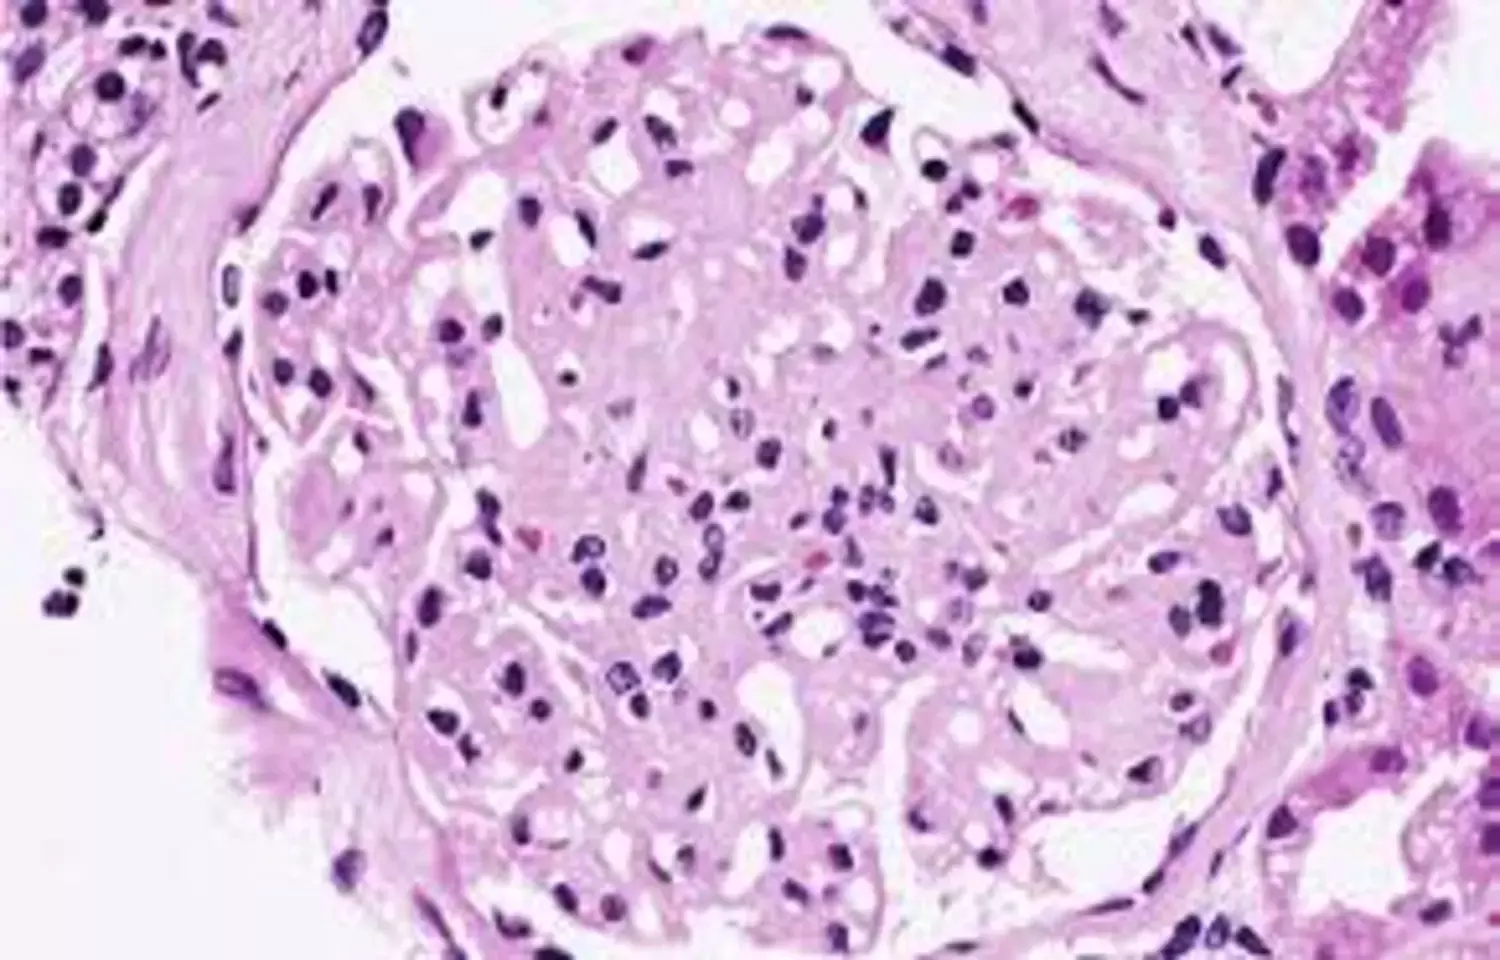

C3 glomerulopathy and primary immune complex membranoproliferative glomerulonephritis generally result in glomerular C3 deposition and progressive, irreversible kidney damage. The efficacy and safety of pegcetacoplan, a complement C3 and C3b inhibitor, have remained uncertain in these conditions. Investigators conducted a phase three, double blind, placebo controlled trial involving adolescents and adults with C3 glomerulopathy or primary immune complex membranoproliferative glomerulonephritis, including patients with native kidney disease as well as those with disease recurrence after kidney transplantation. Participants were randomly assigned to receive pegcetacoplan or placebo. The primary outcome assessed changes in urinary protein excretion over time.

Results showed that patients treated with pegcetacoplan experienced a substantially greater reduction in proteinuria compared with those receiving placebo. A higher proportion of patients in the pegcetacoplan group met composite renal outcome criteria, including stabilization of estimated glomerular filtration rate and meaningful reductions in urinary protein levels. Improvements in proteinuria were also more frequent in the pegcetacoplan group. Among patients with evaluable kidney biopsy samples, changes in histologic activity scores did not differ meaningfully between treatment groups. Pegcetacoplan was generally well tolerated and was not associated with a higher rate of adverse events compared with placebo. No serious infections due to encapsulated bacteria were observed, and no cases of kidney transplant rejection or graft loss occurred.

Pegcetacoplan resulted in a significantly greater reduction in proteinuria than placebo in patients with C3 glomerulopathy or primary immune complex membranoproliferative glomerulonephritis, supporting its role as a targeted therapy for complement mediated kidney disease.